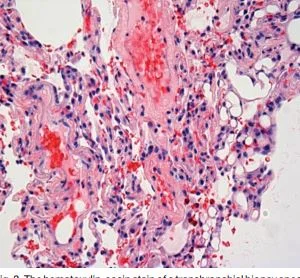

Transbronchial biopsy of a pt with silicone embolus with intra-alveolar hemorrhage and vaculolated glabular deposits of silicone in the interstitial capillaries.

In the case of illegal silicone injections, the proposed mechanisms  of embolization include excessive local tissue pressure, local massage by the illegal practitioner, or direct intravascular injection.   It is thought that large volumes of silicone result in local tissue damage and the silicone eventually gains access to the bloodstream and this results in pulmonary embolization.  This can occur even weeks after an injection.